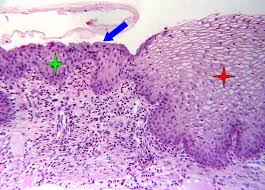

Cervical Squamous Metaplasia Humpath Com Human Pathology from www.humpath.com Because hpv has a predilection for this region, 14 screening must focus on sampling the cells at the transformation zone to adequately detect the presence of dysplasia. In premenopausal women, the transformation zone is fully located on the ectocervix. May 31, 2018 · the transformation zone of the cervix is the region where squamous epithelium replaces glandular epithelium in a process called squamous metaplasia. It corresponds to the area of cervix bound by the original squamocolumnar junction at the distal end and proximally by the furthest extent that squamous metaplasia has occurred as defined by the new squamocolumnar junction. The cervix or cervix uteri (latin, 'neck of the uterus') is the lower part of the uterus in the human female reproductive system.the cervix is usually 2 to 3 cm long (~1 inch) and roughly cylindrical in shape, which changes during pregnancy. Edited by frappart l, fontaniere b, lucas e, sankaranarayanan r. Immature squamous metaplasia (see comment) Though koilocytes can be found in lesions in a number of locations, cervical cytology samples, commonly known as pap smears, frequently contain koilocytes.

Because hpv has a predilection for this region, 14 screening must focus on sampling the cells at the transformation zone to adequately detect the presence of dysplasia. In order to visualize koilocytes collected from the cervix, the tissue is stained with the papanicolaou stain. The transformation zone of the cervix (where columnar and squamous cells meet) is in a continuous process of repair, and squamous metaplasia and inflammation may block a gland orifice. Immature squamous metaplasia (see comment) The endocervical columnar cells continue to secrete but are covered by squamous epithelium, forming a mucinous retention cyst. Squamous metaplasia transitional (urothelial) metaplasia tuboendometrioid metaplasia inflammatory / infectious: May 31, 2018 · the transformation zone of the cervix is the region where squamous epithelium replaces glandular epithelium in a process called squamous metaplasia. It corresponds to the area of cervix bound by the original squamocolumnar junction at the distal end and proximally by the furthest extent that squamous metaplasia has occurred as defined by the new squamocolumnar junction. In premenopausal women, the transformation zone is fully located on the ectocervix. It corresponds to the area of cervix bound by the original squamocolumnar junction at the distal end and proximally by the furthest extent that squamous metaplasia has occurred as defined by the new squamocolumnar junction. In premenopausal women, the transformation zone is fully located on the ectocervix. The cervix or cervix uteri (latin, 'neck of the uterus') is the lower part of the uterus in the human female reproductive system.the cervix is usually 2 to 3 cm long (~1 inch) and roughly cylindrical in shape, which changes during pregnancy. Edited by frappart l, fontaniere b, lucas e, sankaranarayanan r.

Edited by frappart l, fontaniere b, lucas e, sankaranarayanan r. Squamous metaplasia transitional (urothelial) metaplasia tuboendometrioid metaplasia inflammatory / infectious: Immature squamous metaplasia (see comment) May 31, 2018 · the transformation zone of the cervix is the region where squamous epithelium replaces glandular epithelium in a process called squamous metaplasia. Because hpv has a predilection for this region, 14 screening must focus on sampling the cells at the transformation zone to adequately detect the presence of dysplasia.